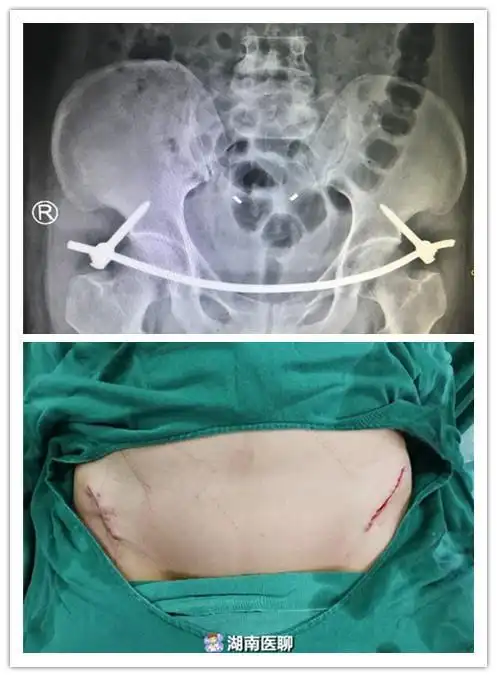

55岁女子车祸骨盆骨折手术后像没事人仅腰上两个小口子

钱红艳虽然保住了性命,但由于伤势过重,骨盆以下被彻底截肢!